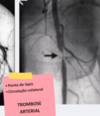

OAA - tem circulação colateral?

NÃO

tem circulação colateral?

SIM